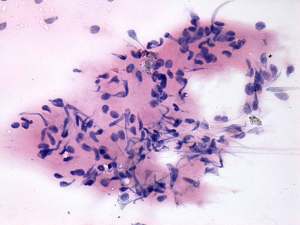

Cytology was performed and resulted in thyroiditis. There were scattered number of lymphocytes and multinucleated giant cells were also found.

The presence of multinucleated giant cells composed of epithelioid cells resembles that observed in de Quervain's thyroiditis. This type of multinucleated cells occurs rarely in autoimmune thyroiditis.